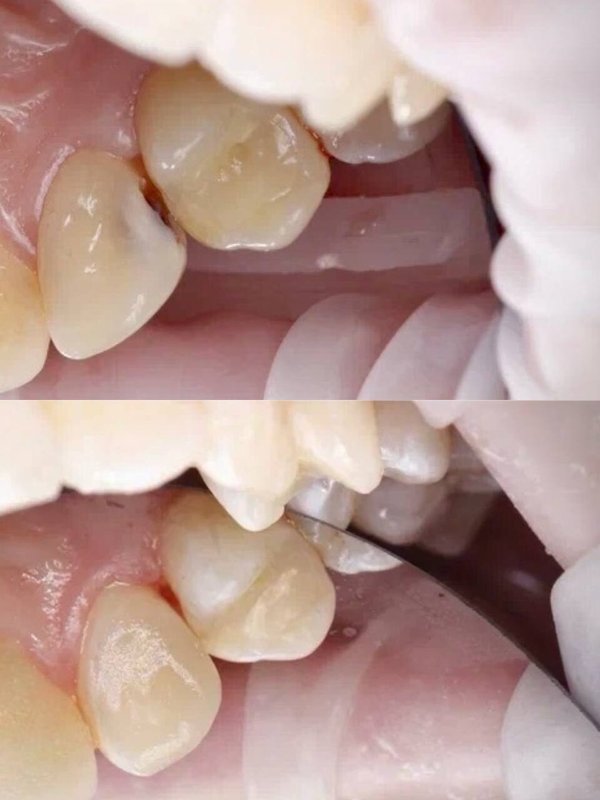

Фотогалерея

Использует техники микропротезирования для восстановления отдельных поврежденных зубов. Устанавливает виниры, вкладки и накладки.

Предлагает различные виды несъемных протезов, такие как металлокерамические коронки, коронки E-max, коронки из диоксида циркония и мостовидные конструкции.

- Использует техники микропротезирования для восстановления поврежденных зубов.

- Устанавливает виниры, вкладки и накладки, что позволяет достичь естественного и эстетически привлекательного результата, а также сохранить здоровье зуба.